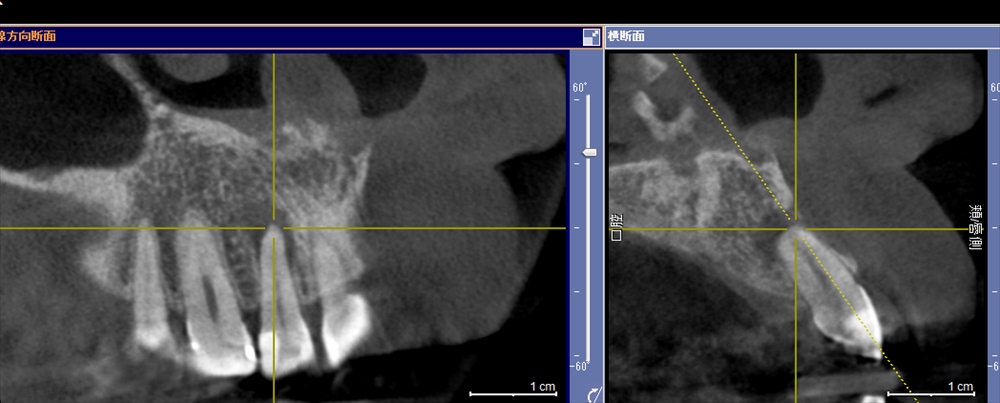

前歯の違和感、はれた感じがする。右上2何かあるぞ。

歯科ドックで精密検査 骨に穴があいている!!!

詳しく原因を調べます。

根尖性周囲炎でした。

ここまで骨がないとは。精密検査だからわかる事です。

本日から精密根管治療スタート。ラバーダムをして

根管を明示。ストレートラインアクセス

感染が見えてきました

術前:右 術後:左 綺麗になった!!これで保存ができます!!次回で根管治療終了。2回で終了